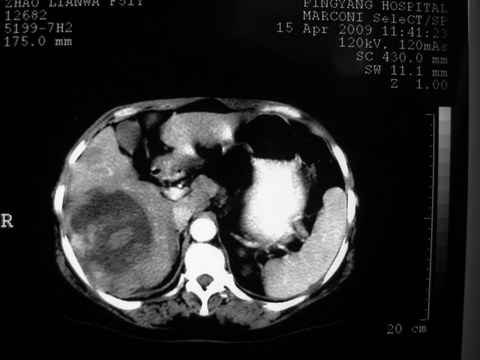

患者 女 51岁 两天前感觉上腹疼,无明显诱因,b超示肝右叶囊实性占位,边缘清楚,其内回声不均匀,ct增强如图,大家看看是什么 ,病人一年前及两月前b超检查只是提示胆囊炎

外院术后,证实肝癌合并出血

特点:1,病灶发展迅速,(2月前正常)[br] 2,囊实性,且并边界清晰光滑,呈右后叶赘生性。囊性区无强化,实性部分较多轻度强化,边界欠清。考虑囊腺癌或囊腺瘤。

出病理 中分化肝细胞癌合并出血